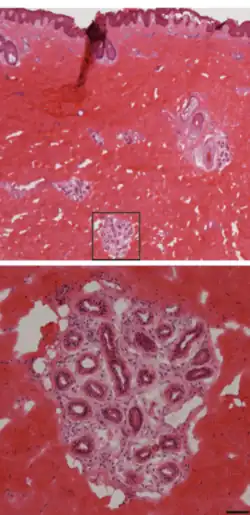

La glándula sudorípara es una glándula[4] que está situada en la dermis reticular e hipodermis y consta de largos y delgados tubos, cerrados por el extremo inferior, donde se juntan, formando un ovillo.[5] Por los poros que se abren al exterior, segregan el sudor, grasa sebácea líquida, con sabor salado, y una textura parecida a la orina. Es una parte fundamentel de la función sudomotora.

Están formadas por un glomérulo secretor y un conducto excretor largo que desemboca directamente en un orificio de la superficie de la piel.[10]

El glomérulo se encuentra en la profundidad de la piel, cerca de la dermis.

La porción secretora o adenómero es de tipo acinar, con una luz estrecha, está formado por epitelio cúbico secretor.

La zona basal del acino está formada por célula mioepiteliales contráctiles, una membrana basal y terminaciones nerviosas.

El conducto es largo y está constituido por dos capas celulares: ductal luminal y ductal basal, no secretoras.[11]